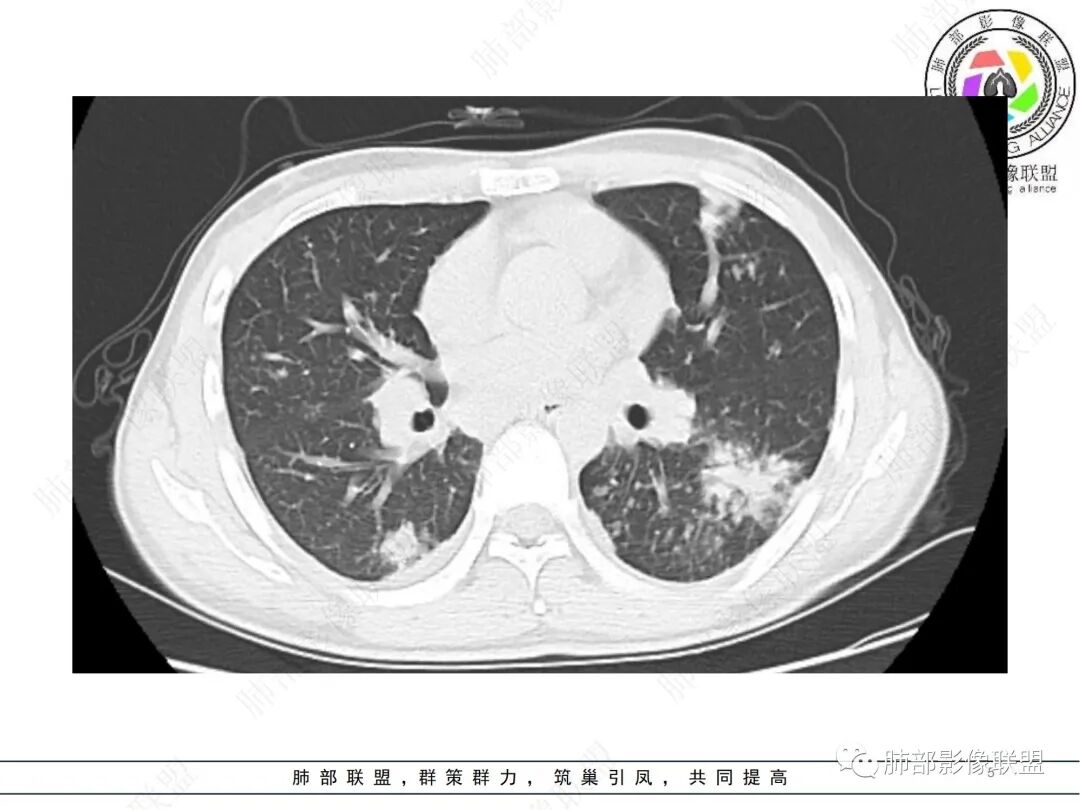

1.临床特点:男,35岁,咳嗽咳痰一周。辅助检查示:肿瘤指标(-)。

2.影像特点:双肺多发实变,结节状、斑片状、斑点状影,成簇分布趋势,密度不均(部分密度较高),多数位于胸膜下或支气管血管束周围,与支气管关系密切,部分气管壁钙化,部分实变影周围多发弥漫粟粒结节呈星系征样改变,呈轻度渐进性强化,未见空洞。双肺门及纵隔淋巴结肿大,并显示融合,其中后纵隔肿大淋巴结间可见血管影穿行。右侧胸膜增厚伴少量胸腔积液。

3.病例小结:男,35岁,咳嗽咳痰一周,胸部CT提示:双肺多形、多态、多部位的分布,淋巴结肿大,胸膜增厚、胸腔积液,气管壁关系密切,这些可符合结核。

年轻患者,无免疫缺陷,继发性肺结核很少侵犯淋巴结,且无TB中毒症状,双肺门及纵隔淋巴结肿大,应想到结节病可能,不典型之处在于,小叶间隔、叶间裂、血管支气管束较少观察到串珠状小结节影,胸膜增厚伴积液也很少见于结节病。